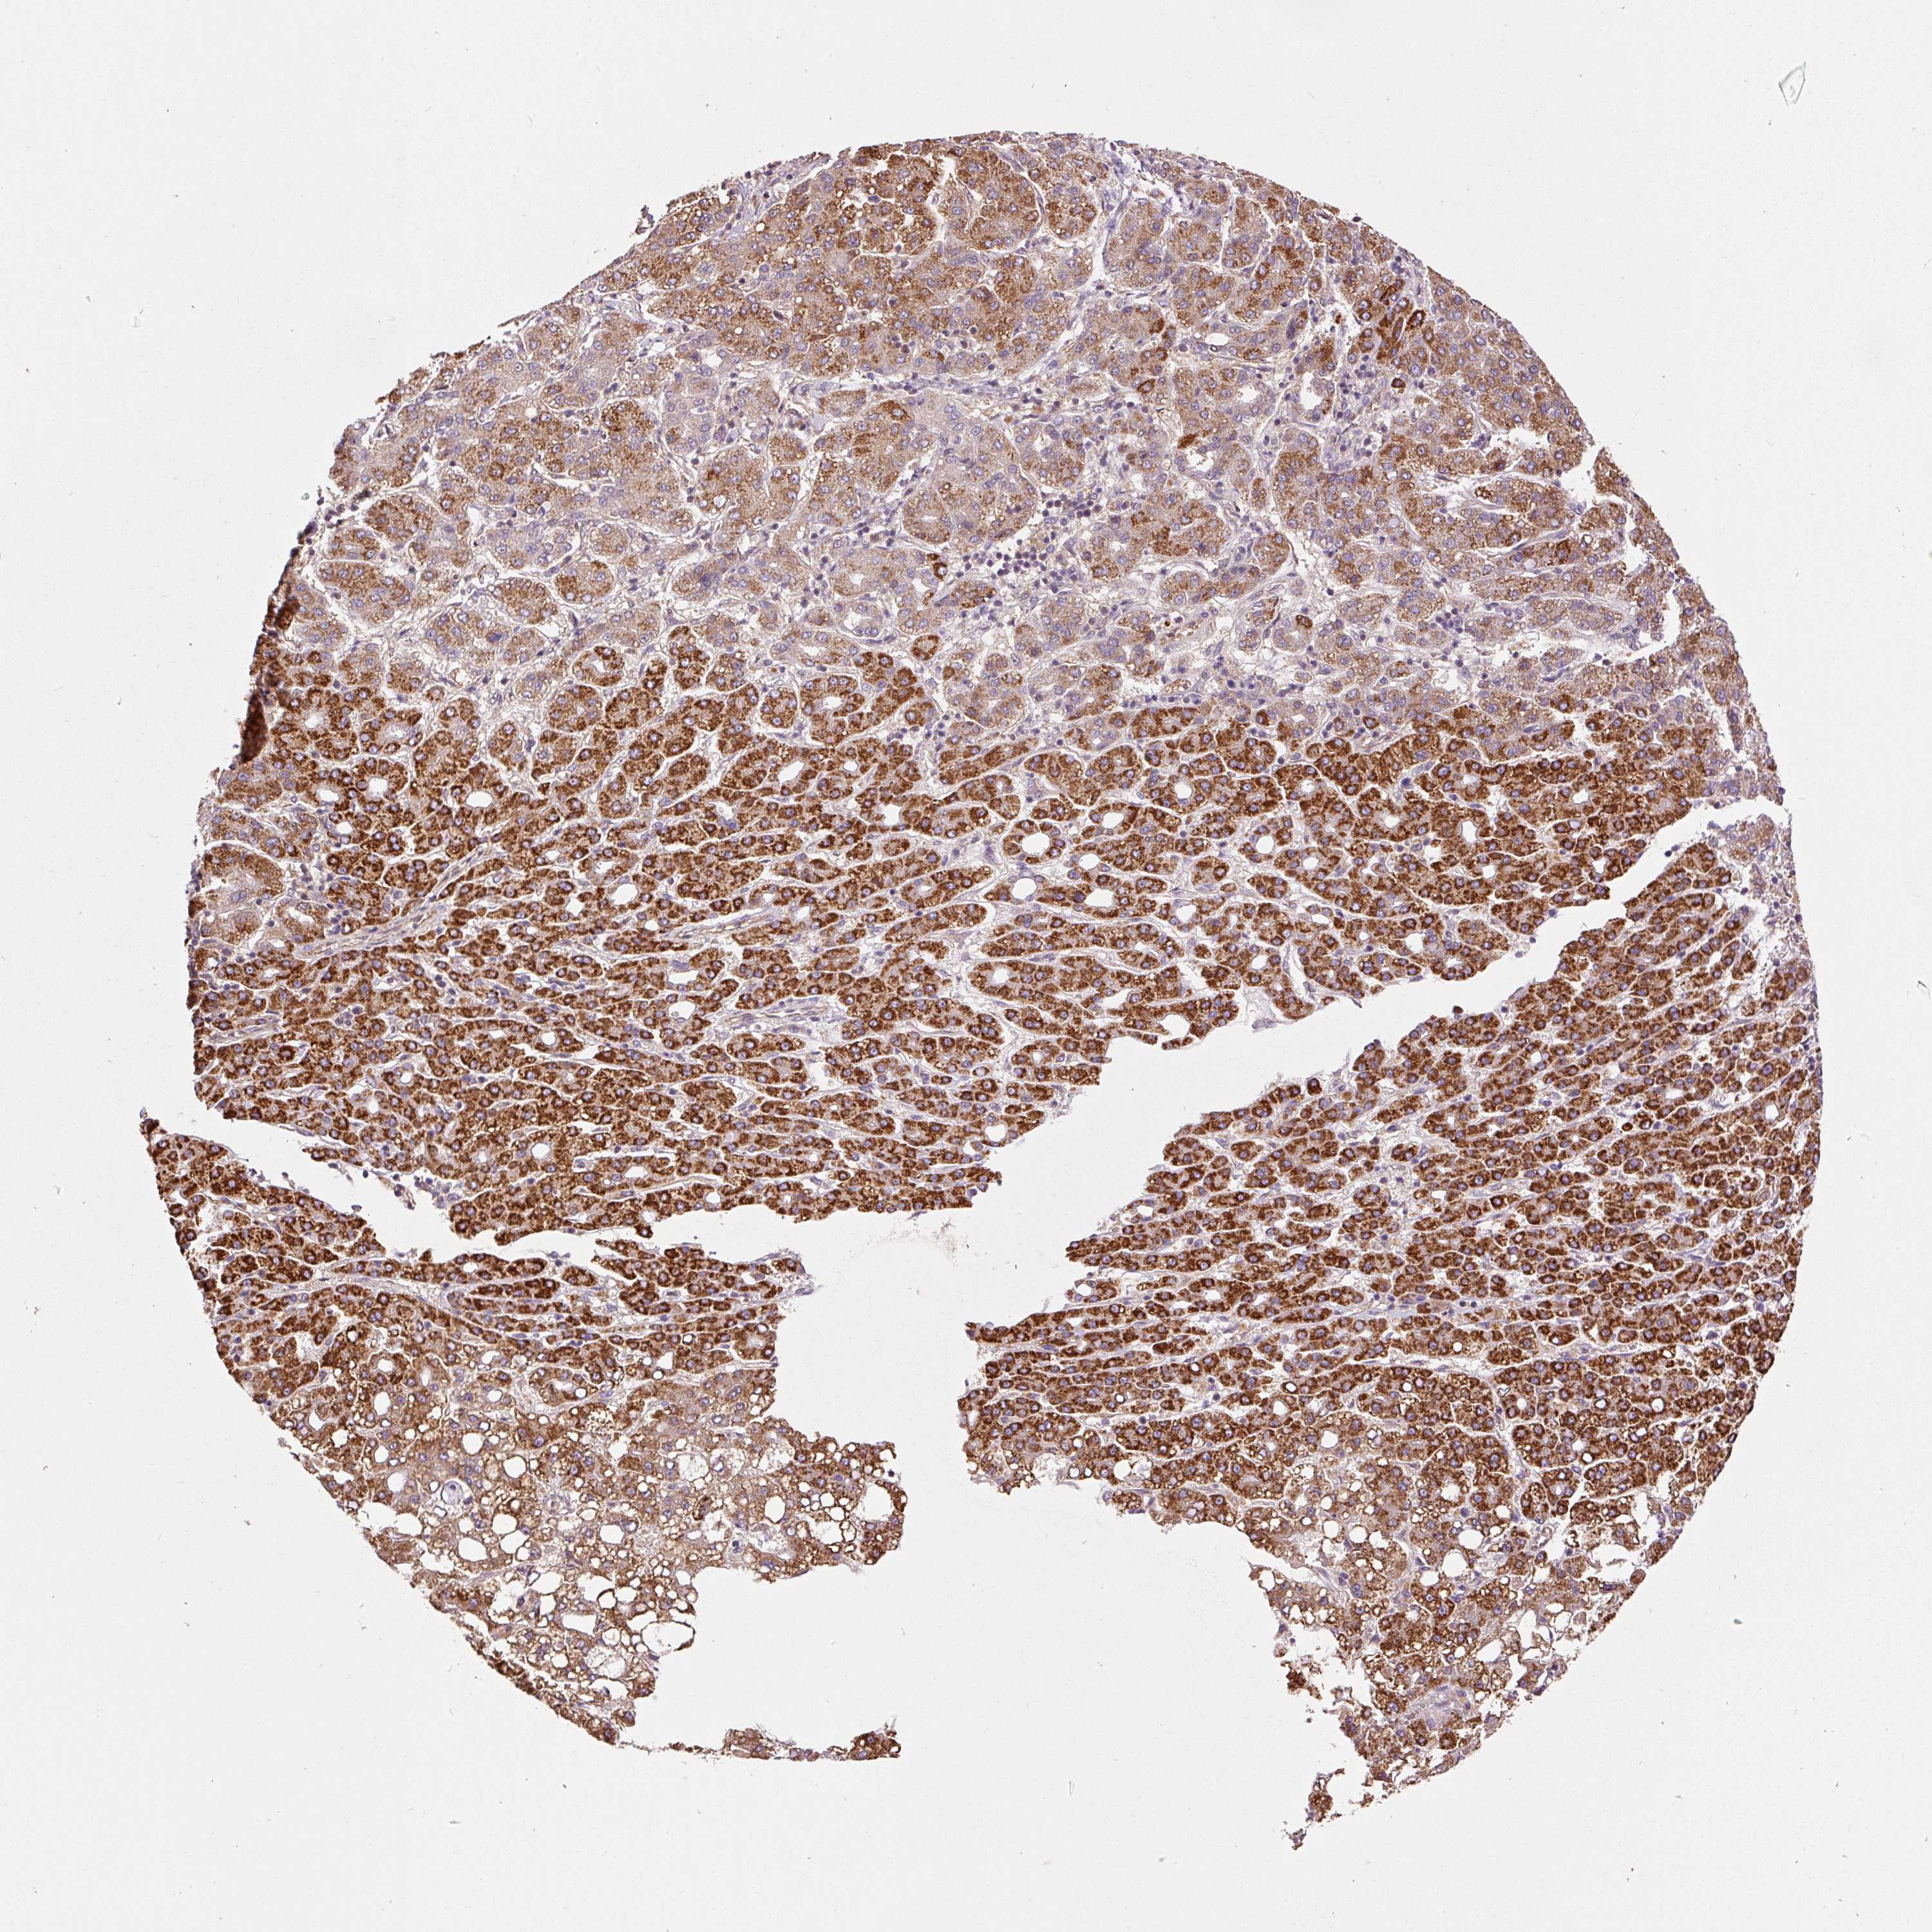

LIVER CANCER - Protein expressioni

A mouse-over function shows sample information and annotation data. Click on an image to view it in a full screen mode. Samples can be filtered based on level of antibody staining by selecting one or several of the following categories: high, medium, low and not detected. The assay and annotation is described here.

Note that samples used for immunohistochemistry by the Human Protein Atlas do not correspond to samples in the TCGA dataset.

Antibody stainingi

Antibody staining in the annotated cell types in the current human tissue is reported as not detected, low, medium, or high, based on conventional immunohistochemistry profiling in selected tissues. This score is based on the combination of the staining intensity and fraction of stained cells.

Each image is clickable and will lead to virtual microscopy that enables deeper exploration of all samples and also displays staining intensity scores, fraction scores and subcellular localization as well as patient and tissue information for each sample.

Antibody HPA051162

Antibody HPA053502

Antibody CAB018734

Staining

High

Medium

Low

Not detected

Intensity

Strong

Moderate

Weak

Negative

Quantity

>75%

75%-25%

<25%

None

Location

Nuclear

Cytoplasmic/membranous

Cytoplasmic/membranous,nuclear

Cholangiocarcinoma

Carcinoma, Hepatocellular, NOS